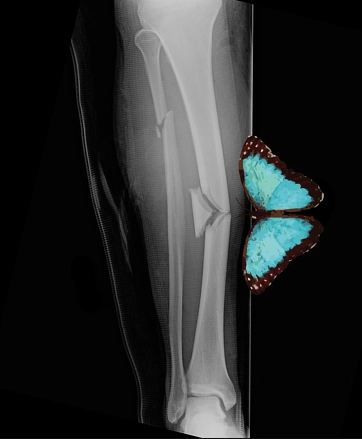

Fragment din mijloc triunghiular

A

fragment in aripa de fluture